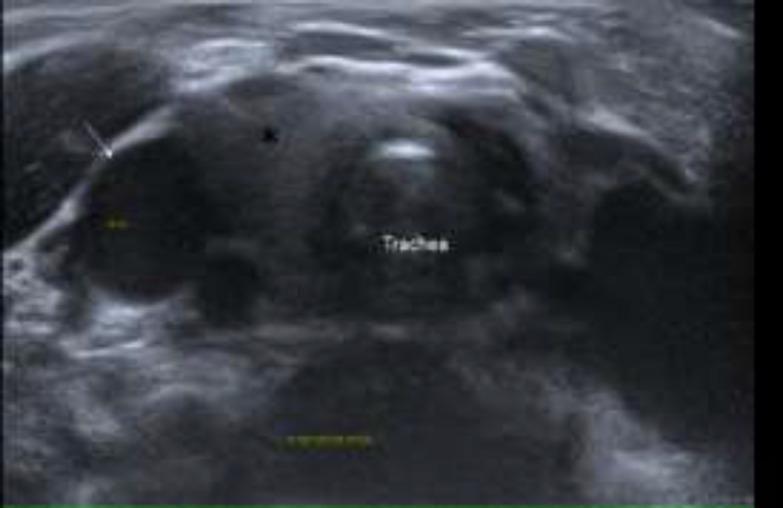

We report two cases with atypical clinical presentation of ectopic thymus and superior herniation of normal thymus. Both of the patients manifested as intermittent midline mass at the suprasternal region during Valsalva manuevre. Unique ultrasound features with the location along the thymic descent together with dynamic assessment of the organ movement were essential to reach the correct diagnosis. Conservative approach was considered in these patients considering the necessity of thymus in the process of puberty.

我们报告两例具有非典型临床表现的异位胸腺及正常胸腺向上疝出的病例。两名患者在瓦尔萨尔瓦动作时均表现为胸骨上区域间歇性中线肿块。沿胸腺下降路径的独特超声特征以及对器官运动的动态评估对于做出正确诊断至关重要。考虑到青春期胸腺的必要性,对这些患者采取了保守治疗方法。